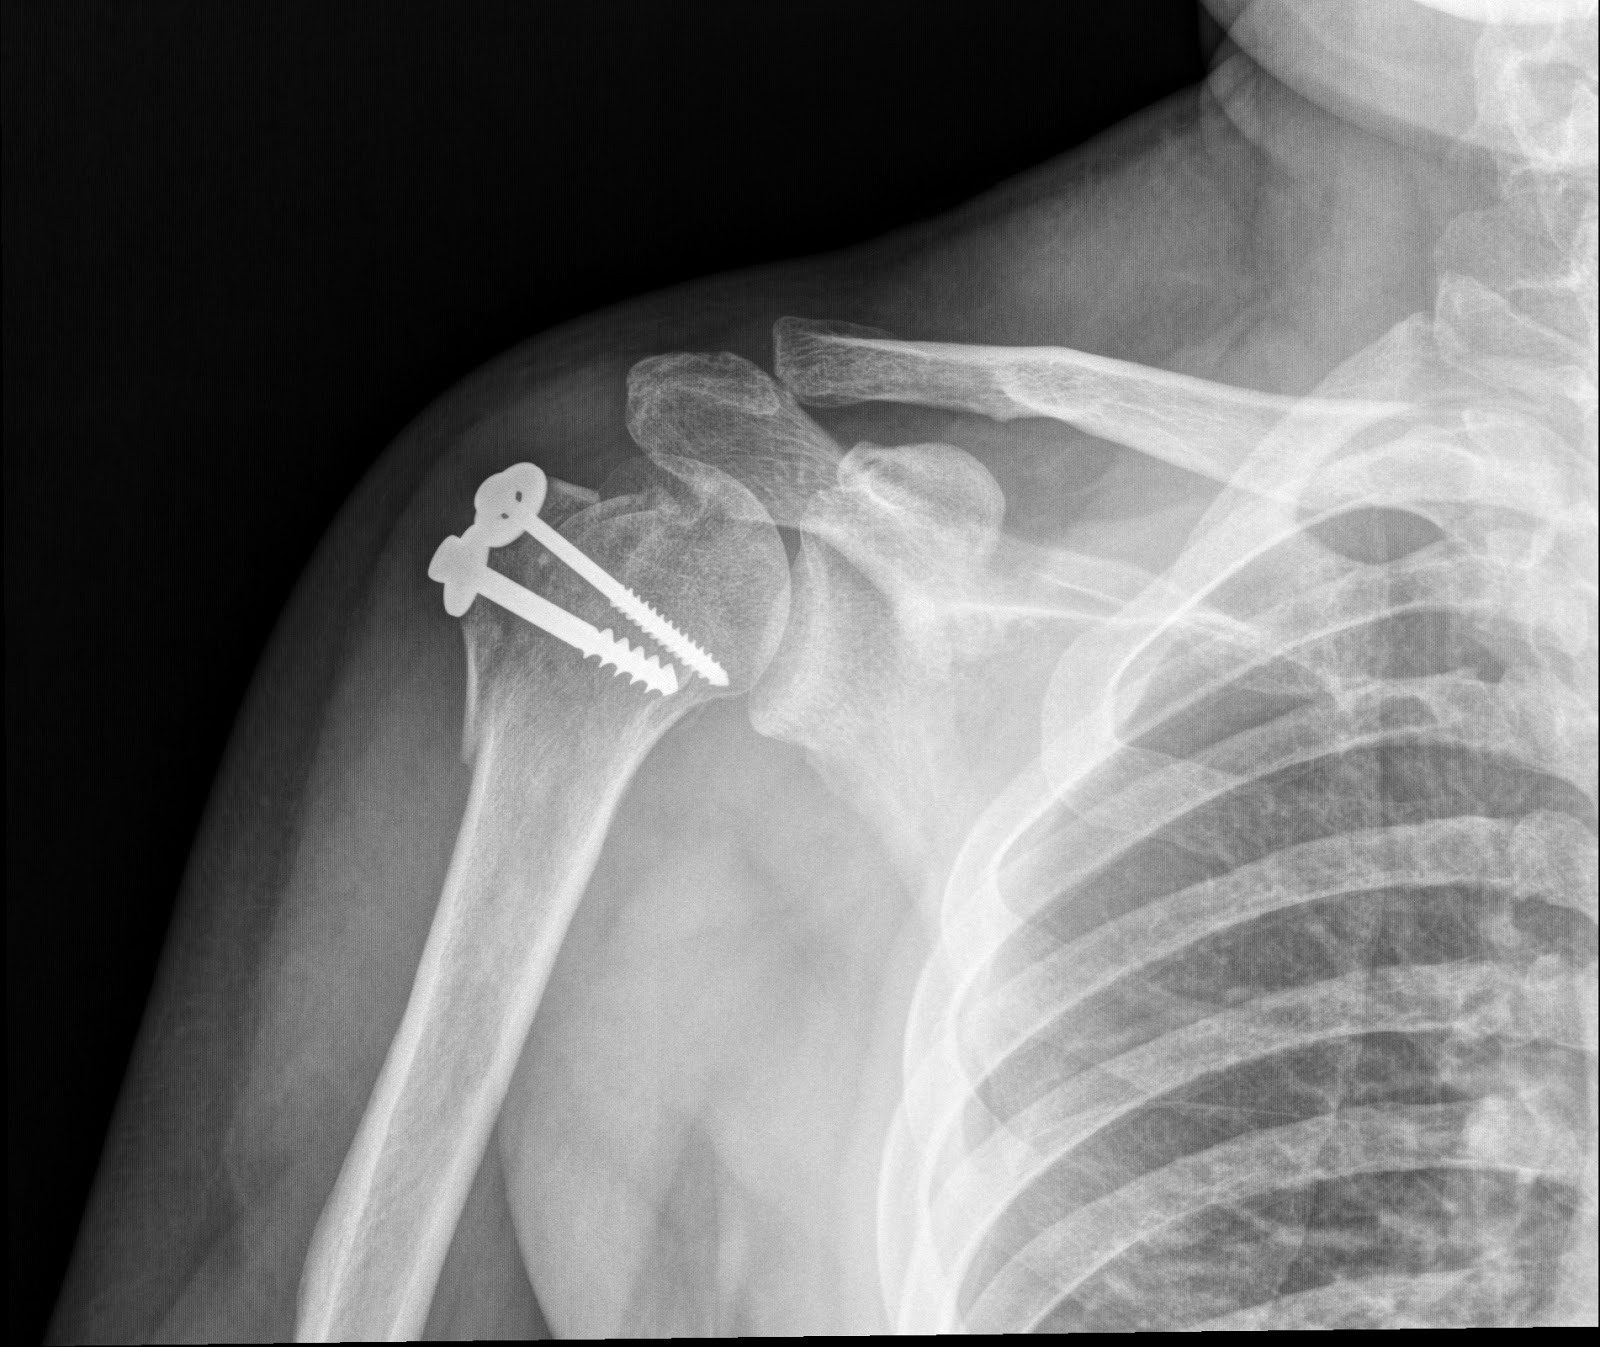

Shoulder X Ray post Operation – Radiology Imaging